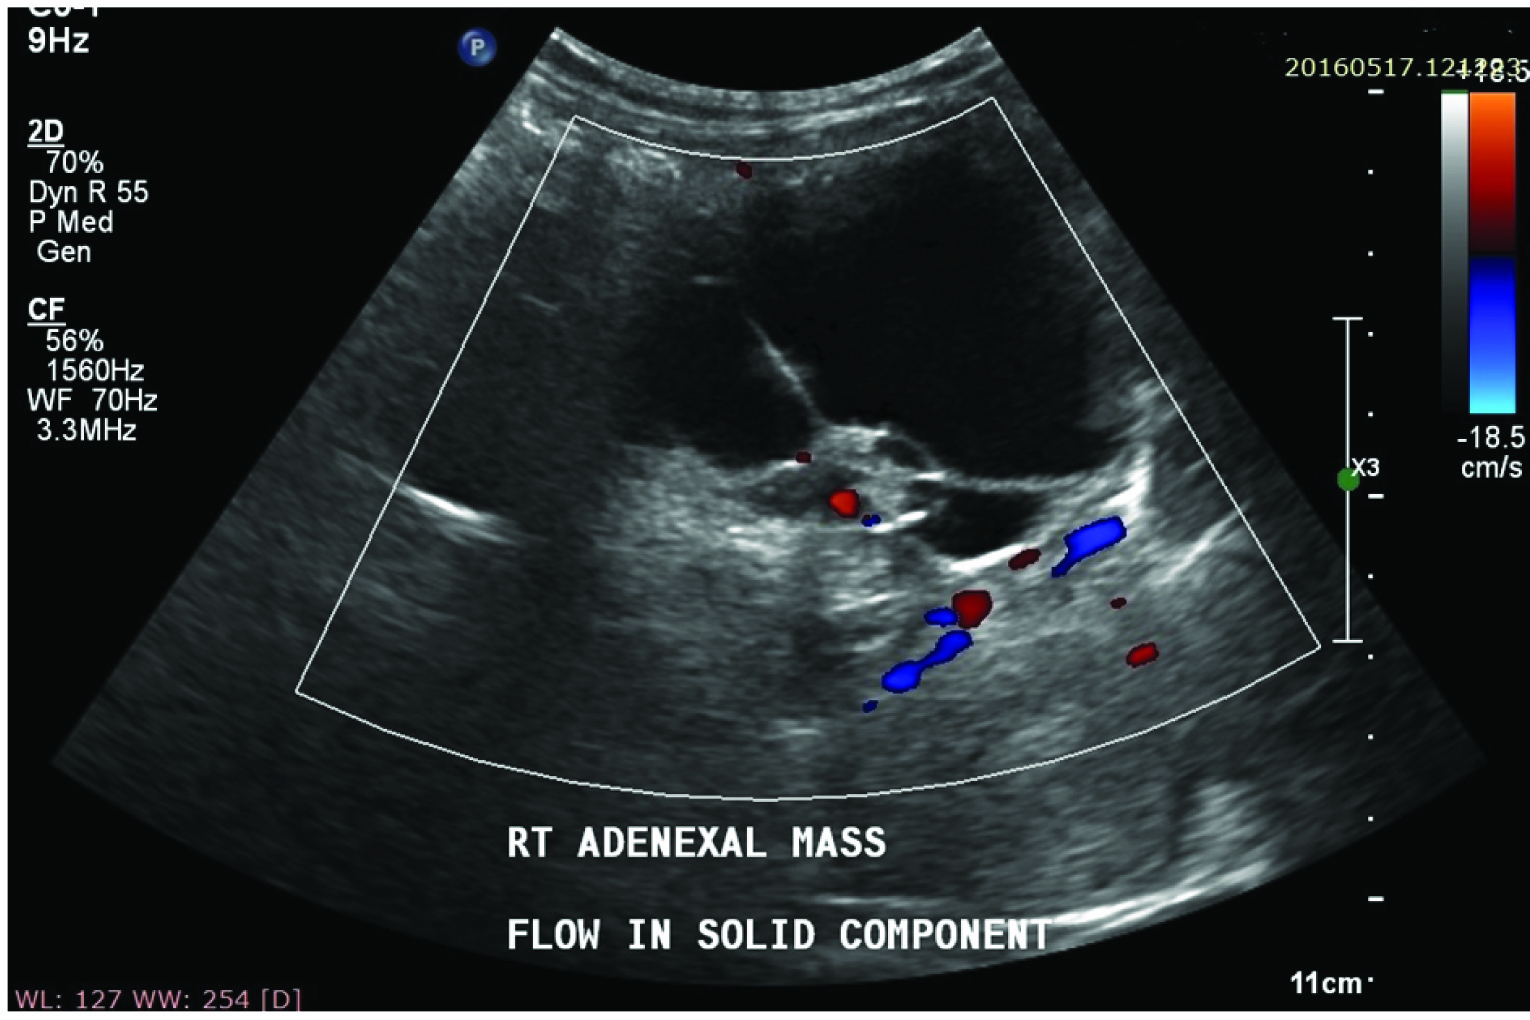

Complex adnexal mass showing flow in solid component on Colour Doppler scan.

Total 50 patients were included in the study. These patients were examined with a real time sonography equipment- Colour Doppler USG SSA 350A/31 and or Aloka prosound SSD- 4000SV, using sector transducer of frequency 3-5 MHz through a transvesical approach, B-Mode USG, Colour Doppler and spectral Doppler was performed. Morphological indexing of adnexal masses was done according to Kujrak et al., morphological scoring system [Table/Fig-1] [7]. On B- Mode USG both solid and cystic components are seen in complex adnexal masses [Table/Fig-2]. Parameters taken in Colour Doppler were flow study, vessel arrangement, and vessel morphology and vessel location [Table/Fig-3]. Parameters considered for malignancy in spectral Doppler were Resistive Index (RI) and Pulsatility Index (PI). If required, endo-vaginal sonography was also performed with a 4-8 MHz vaginal transducer. Statistical analysis was performed with SPSS version 19. Fisher’s-exact test and Chi-square with Yates correction were used.

Ultrasonic signs on morphologic assessment of malignant ovarian tumours include multilocular or multiple cysts, thick or irregular septa or walls, poorly defined borders, mural nodules, solid components and echogenic elements. On colour Doppler presence of vascularity, central site of vessels, random vessel arrangement and abnormal vessel morphology were suggestive of malignant ovarian lesion. Spectral Doppler findings suggestive of malignancy are when Resistive Index (RI) value is ≤ 0.4 and Pulsatility Index (PI) value is ≤ 1.0 [10]. High resistive index and pulsatility index values are suggestive of benign pathology in adnexal masses [Table/Fig-9].